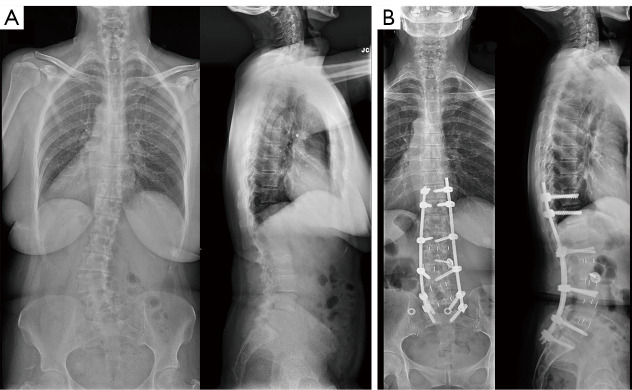

Abstract Image